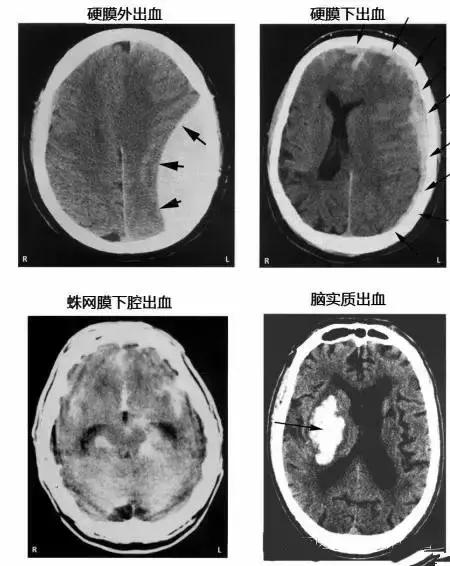

各种颅内出血

几种类型脑出血的CT表现